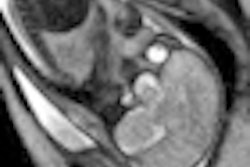

How timely, then, that physicians at Charité University Hospital in Berlin captured the process of a fetus moving into the birth canal with MR images for the very first time. Click here to read about and see an image from this radiology first.